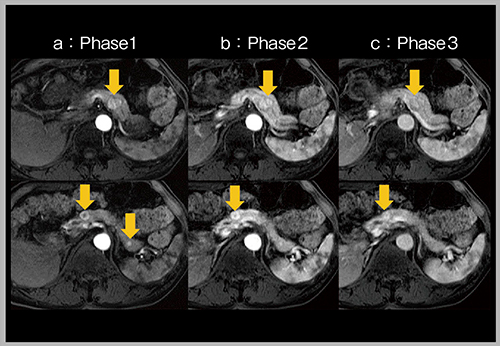

肝細胞がん(HCC)は動脈相で濃染し,門脈相から遅延相にかけてwash-outするが,その際,辺縁部にリング状の濃染,すなわちenhancing capsuleを呈する。enhancing capsuleは,LI-RADSでは主要項目であり,HCC診断の確信度が向上するとされている。HCCの精査のため当院に紹介された2症例について,DISCOを用いて6相で撮像した動脈相の画像(図4)を見ると,a(87歳,女性,C型肝炎)は最初に全体が濃染し,その後にリング状となる典型的なHCCのパターン,b(72歳,男性,C型肝硬変)は最初からリング状に濃染し,内部が壊死したパターンを呈していた。このように多時相を取得することで,腫瘍の血行動態をより詳細に検討することができる。

一方,日本で多用される肝特異性造影剤は,肝実質に急速に取り込まれるためenhancing capsuleが不明瞭となり,しばしば描出されない。そこで,門脈相よりも前の後期動脈相であれば,enhancing capsuleをより高頻度にとらえられると考えた。実際の178症例で検討したところ,門脈相のみでLI-RADSのクライテリアのLR-5(ほとんどすべてがHCC)に分類できたのは90症例であったが,動脈相の6相で評価したところ95症例となり,HCC診断の確信度が向上する結果となった1)。

図4 View sharing(DISCO)による動脈相の多時相化(HCC精査)